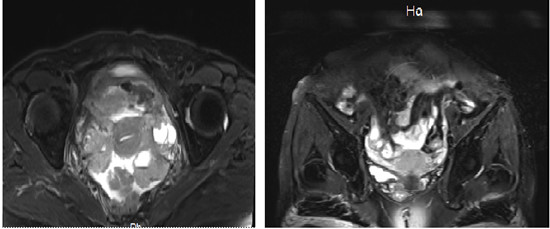

我们可以看到治疗前(第一张图),盆腔内多发肿瘤占位聚集成团,正常结构消失,大量微小病灶散布周围。治疗后(第二张图)多发肿瘤均消失,正常结构显现,目前患者正在巩固治疗中。

6月1日,孔主任首先在最短的时间内为患者行“彩超引导下人工腹水腹腔穿刺置管术”;其次,为患者行“腹腔热灌注+静脉用药”双通路热灌注化疗,共两个周期,并间断行深部热疗多次。肿瘤深部热疗原理是采用物理加热方式治疗肿瘤,利用物理能量在组织中沉淀产生热效应,使肿瘤组织上升到有效治疗温度(40-43℃),并维持一定时间,使肿瘤细胞变性坏死,又不损伤正常细胞。还能提高肿瘤对放疗、化疗的敏感性,使抗癌效应倍增。两个周期治疗结束后,复查核磁共振提示原双侧附件区、子宫直肠陷凹病灶消失,抗癌原降至正常水平。